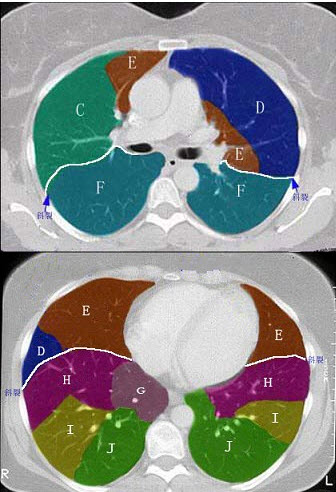

结合肺段模式(见图),选出右肺下叶的组成( )

A:F

B:F+G

C:F+G+H

D:F+G+H+I

E:F+G+H+I+J